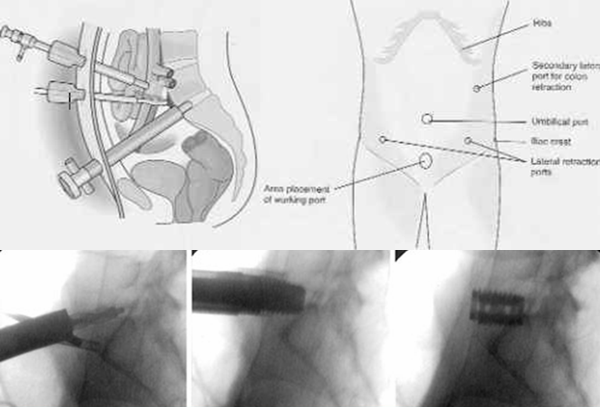

从80-90年代起,随着微创理念在外科的生根发芽和腹腔镜技术的兴起,与BAK诞生的同期,脊柱外科医生开始对前路手术入路进行了改良。1991年,Obenchain进行了首例腹腔镜下椎间盘切除术[20]。随后德国人Zucherman 在1995年进行了首例腹腔镜下ALIF( Laparoscopic ALIF,LALIF) [21],国内吕国华团队于1998年起开始行LALIF[22](图9)。

早期文献报道该技术具有微创优势明显,手术出血量少、患者恢复快、住院时间短等优点。随着腹腔镜下的cage的出现,明显提高了手术融合率高 [23,24]。随后的时期,LALIF在世界各地得到如火如荼的开展,然而时至今日,LALIF的应用已经是凤毛麟角,为什么LALIF没有像腹腔镜胆囊切除术那样成为胆囊切除的主流术式呢?

图9 LALIF 上图 LALIF的示意图,下图LALIF术中的侧位X线片